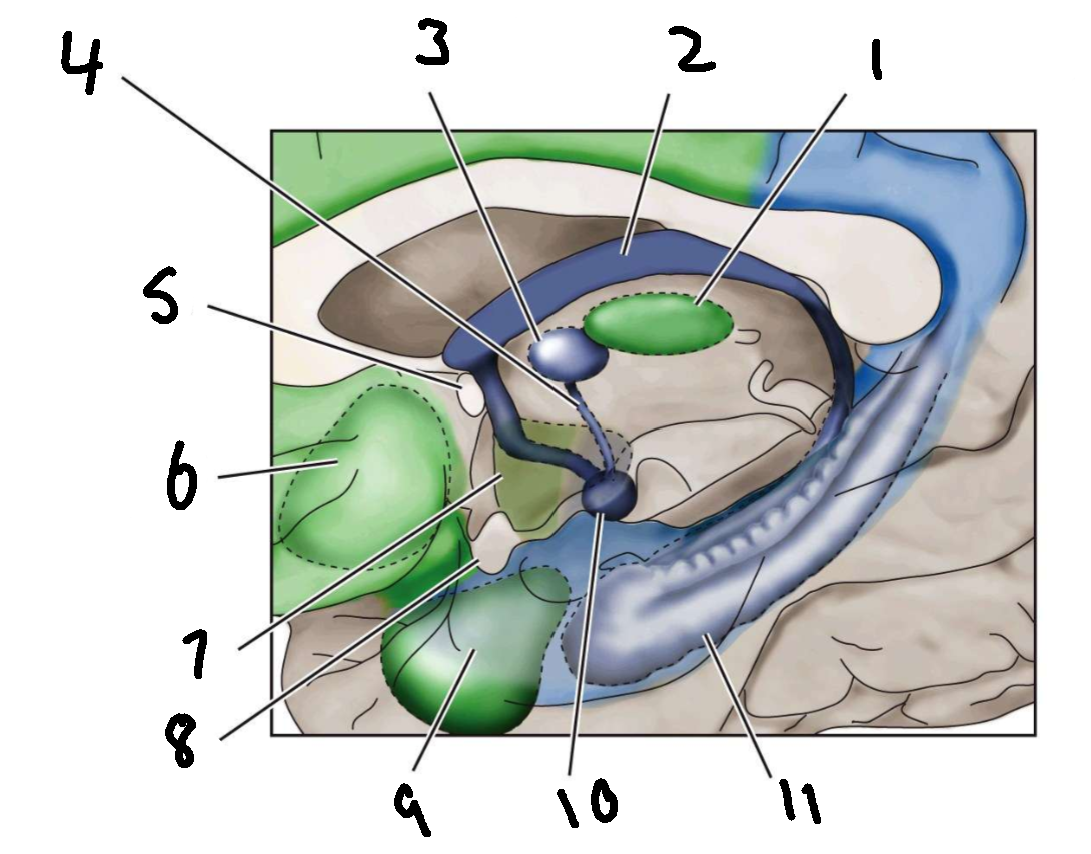

What is 1?

mediodorsal nucleus of the thalamus

What is 2?

fornix

What is 3?

anterior nucleus of the thalamus

What is 4?

mammillothalamic tract

What is 5?

anterior commissure

What is 6?

ventral basal ganglia

What is 7?

hypothalamus

What is 8?

optic chiasm

What is 9?

amygdala

What is 10?

mammillary body

What is 11?

hippocampus